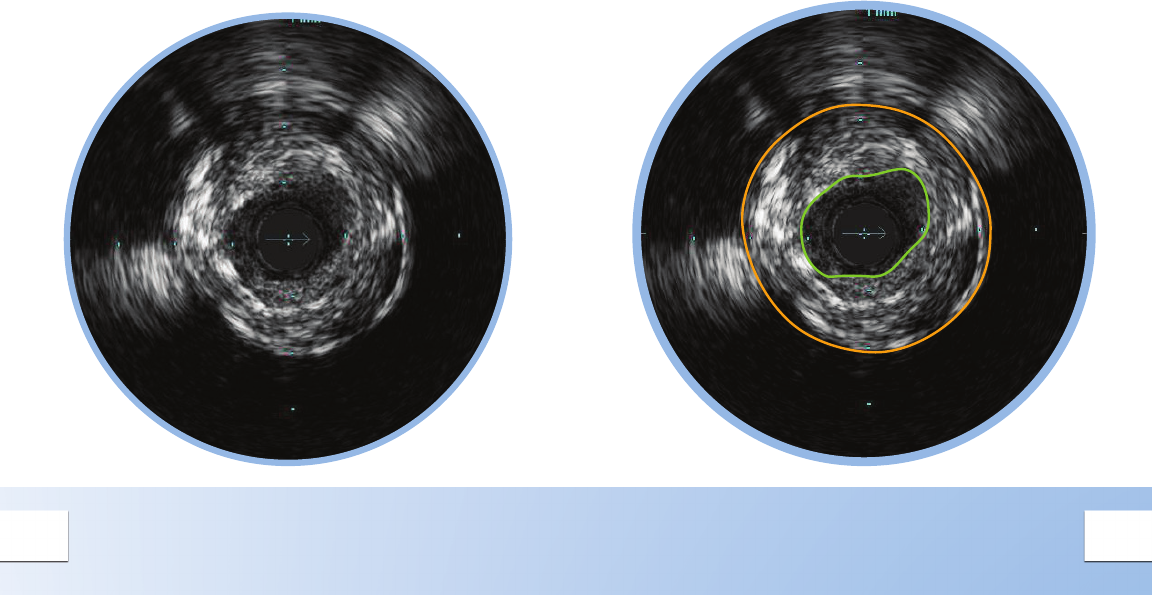

CONCENTRIC MIXED PLAQUE

Concentric plaques are distributed

circumferentially in the vessel.

Concentric plaques tend to occur in areas of

negative remodeling; use of angiography alone

could result in too large a stent diameter.

Mixed plaque is a combination of tissues of varying

echogenecity. The distribution of light and dark

may be distinct, or light and dark variations may be

intermingled as shown here.

Minimum Lumen Area (MLA) can dene a threshold

for a signicant stenosis to determine the need for

catheter-based or surgical intervention.

• MLA < 4 mm2 in LAD, LCX, and RCA vessels > 3

mm in diameter correlates with physiological

signicance1

• MLA < 6 mm2 in left main correlates with FFR <

0.75 indicating physiological signicance1,2,3